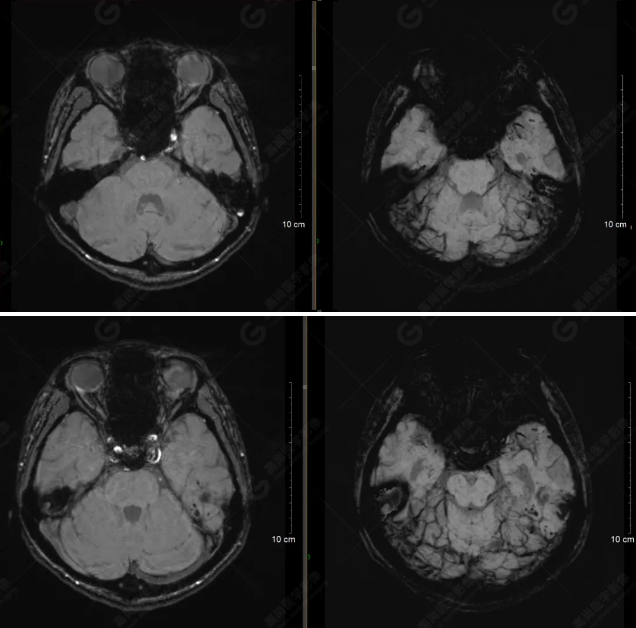

顱腦MRI平掃未見明顯異常,左側(cè)乳突內(nèi)積血,建議補(bǔ)充SWI檢查。(左側(cè)為薄層原始圖像,右側(cè)為后處理5mm圖像)

SWI序列影像表現(xiàn)及診斷

左側(cè)額底及左側(cè)顳葉內(nèi)見多發(fā)斑點狀極低信號影??紤]額顳葉多發(fā)腦挫傷伴微出血、含鐵血黃素沉著,左側(cè)乳突骨折、乳突內(nèi)積血。討論:1、SWI利用不同組織間磁敏感的差異成像并將其放大,通過檢測病灶中的靜脈分布、出血灶和礦物質(zhì)沉積等,有效改善了相關(guān)疾病的診斷,主要應(yīng)用于中樞神經(jīng)系統(tǒng)。2、根據(jù)磁距圖像和相位圖像表現(xiàn),對于鑒別顱內(nèi)出血及鈣化有一定程度的價值,用于彌補(bǔ)MRI對鈣化顯示的不足。

磁敏感加權(quán)成像(SWI) 以T2*加權(quán)梯度回波序列作為序列基礎(chǔ),根據(jù)不同組織間的磁敏感性差異提供圖像對比增強(qiáng),可同時獲得磁距圖像和相位圖像。該技術(shù)早期主要應(yīng)用于腦內(nèi)小靜脈的顯示,近年來經(jīng)過高場磁共振儀的應(yīng)用及相關(guān)技術(shù)的不斷改進(jìn),其臨床應(yīng)用范圍得到了極大的擴(kuò)展。SWI能夠比常規(guī)梯度回波序列更敏感地顯示出血,甚至是微小出血,在診斷腦外傷、腦腫瘤、腦血管畸形、腦血管病及某些神經(jīng)變性病等方面具有較高的價值及應(yīng)用前景。